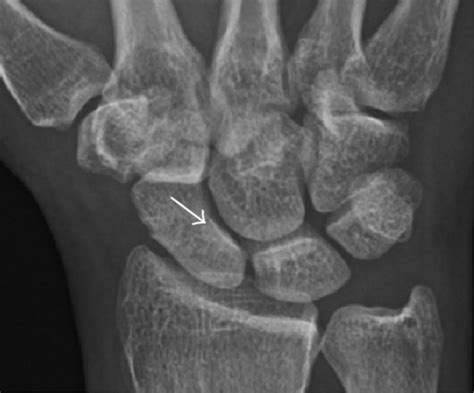

Diagnosing a Broken Scaphoid Bone

Diagnosing a broken scaphoid bone involves a combination of physical examination and imaging tests. A healthcare provider will typically:

• Order imaging tests, such as X-rays, to visualize the bone

However, X-rays may not always show a scaphoid fracture, especially in the early stages. In such cases, additional imaging tests may be required, including:

• Computed tomography (CT) scans

• Magnetic resonance imaging (MRI) scans

• Bone scans

These tests can provide more detailed images of the bone and surrounding tissues, helping to confirm the diagnosis and assess the extent of the injury.